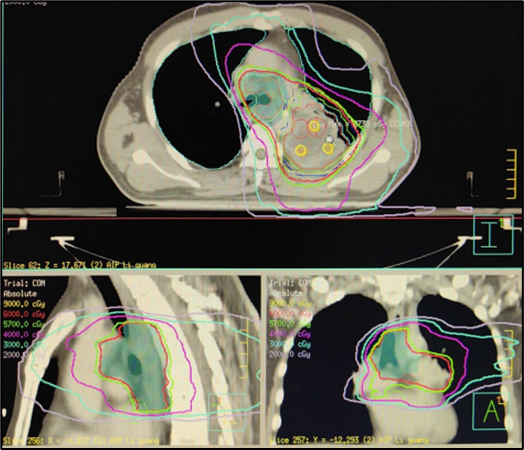

空间分割放疗(Spatially Fractionated Radiotherapy,SFRT )运用了峰谷交替的剂量分布方式,与传统的照射相比,SFRT能有效地治疗肿瘤并保护肿瘤周围正常组织的功能和完整性,具有独特的放射生物学反应机制,如旁观效应、微血管变化和免疫调节等。临床研究显示,无论是巨大的转移瘤还是原发性肿瘤,SFRT都表现出显著的治疗效果,尤其是优秀的肿瘤局部控制率,约90%,并且安全性良好。

自2024年7月起,由卢冰教授率领贵州医科大学附属医院、附属肿瘤医院胸部肿瘤科团队和放射物理师团队率先开展SFRT的临床应用,至今已完成几十例患者的临床治疗。第1例应用SFRT治疗的患者由卢冰教授带领李青松副主任医师、胡银祥高级工程师完成。对一例LA-NSCLC患者在同期放化疗联合免疫维持治疗的标准治疗模式中,放疗采用SFRT,疗程结束时肿瘤明显缩小,定期随访发现肿瘤完全消失(图示),取得了远超常规放疗的临床效果,而且无明显的放疗并发症,病人生活质量满意,可自行驾车外出游玩。

SFRT放射治疗计划